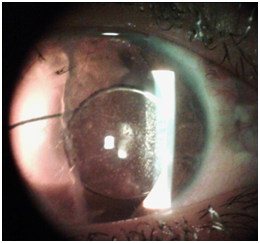

In the first postoperative visit, the eye was slightly injected with periorbital ecchymosis and conjunctival chemosis, anterior chamber was formed, no signs of wound leakage or infection were found. On the second week, neovessels began to grow at the limbal portion at 12 o’clock towards the cornea with mild corneal edema. Neovessels started to penetrate the cornea, intense topical steroids were prescribed and the parents were advised to follow up weekly. Refractive +18D soft contact lens was prescribed and the patient could gain best corrected visual acuity of 20/80. After one month, aggressive neovascularization in the conjunctiva invading the superior one third of cornea was noticed (Figure 2) so the patient underwent conjunctival recession operation and diathermy of the feeding vessel under GA. After two months of the operation, the patient underwent scleral fixation IOL implantation. After six months: pseudophakic retinal detachment was detected and the patient was urgently transferred to vitreo-retinal unit for vitrectomy surgery. The surgery was completed successfully and the patient regained visual acuity of 20/40.

Figure 2 Neovessels growing and invading the cornea.

Figure 3 Scleral fixated IOL in place, corneal neovessels regressed.